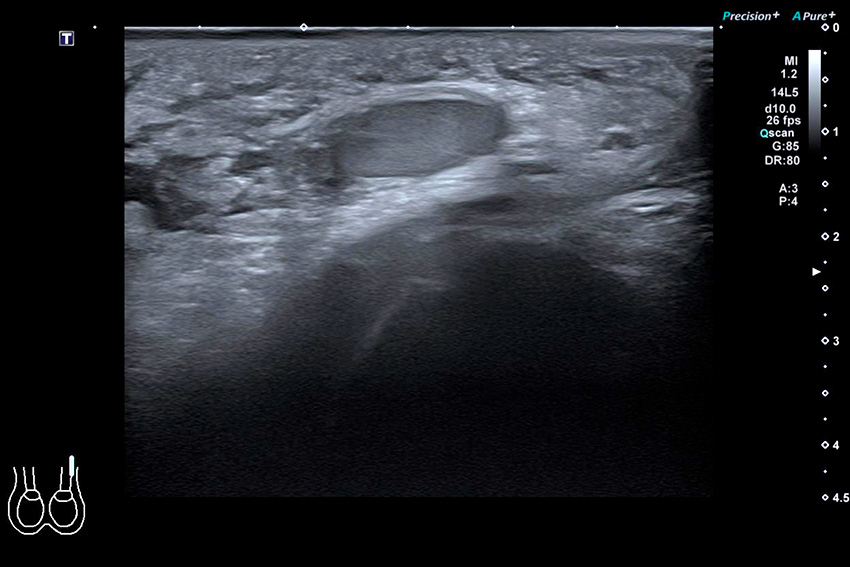

Testistorsion. Höger testikel (till vänster i bild) är storleks­ökad med inhomogen ekogenitet samt nedsatt flödessignal. Normalt utseende av vänster testikel (till höger i bild). Klassisk bild är en förstorad testikel med nedsatt centralvenöst och arteriellt flöde jämfört med den opåverkade sidan. Blodflöde i testiklar är tekniskt svårt att få fram med doppler på barn <2 år. Nedsatt ekogenitet i testikelparenkymet och asymmetrisk testikelförstoring på den påverkade sidan kan tala för torsion. Minskat blodflöde till testikeln på ultraljud har både hög sensitivitet (85–100 procent) och specificitet (98–100 procent) för torsion. Då blodflödet dock i vissa fall kan vara både bevarat och ökat vid testistorsion kan diagnosen inte uteslutas enbart baserat på bedömning av detta. Torsion av funikeln, så kallat »whirlpool sign«, anses vara diagnostisk.